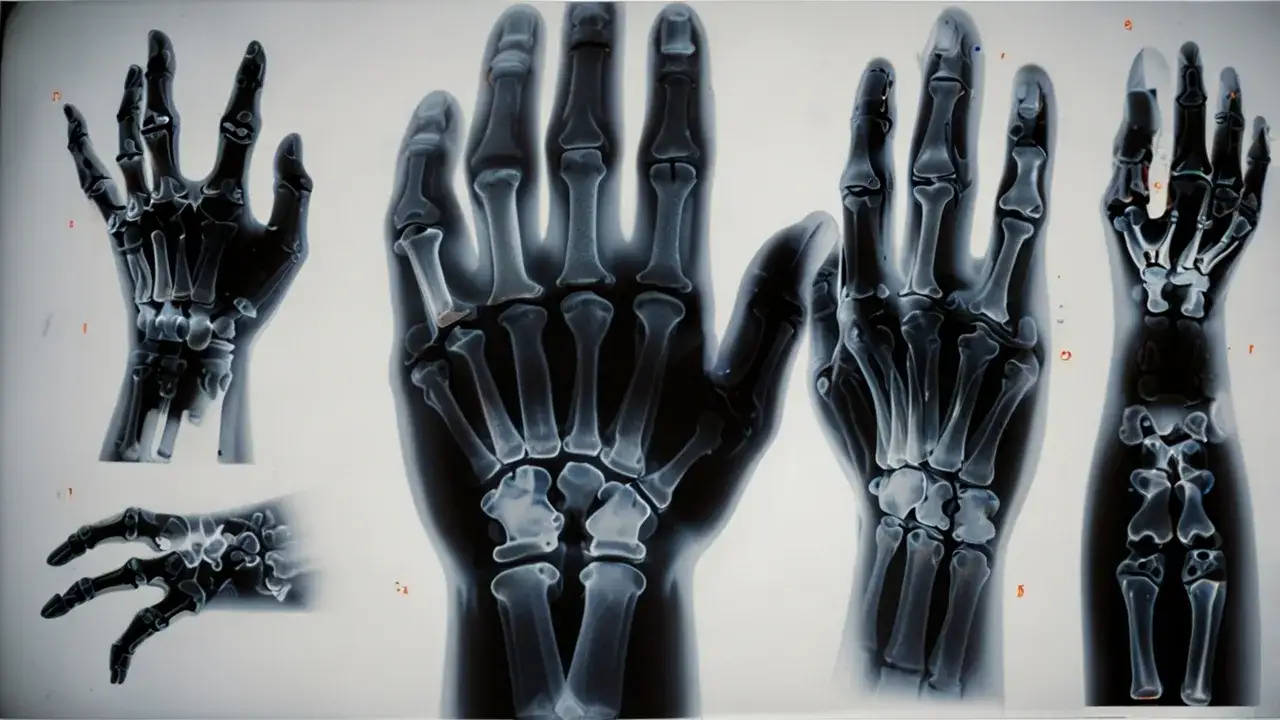

Dokładna diagnoza jest kluczowa dla właściwego leczenia złamanego palca. Lekarz rozpocznie od wywiadu medycznego, pytając o okoliczności urazu i towarzyszące objawy. Następnie przeprowadzi badanie fizyczne, oceniając wygląd, ruchomość i czucie w palcu.

Po wstępnej ocenie, specjalista zleci badania obrazowe. Są one niezbędne do potwierdzenia diagnozy i określenia dokładnego charakteru złamania.

Badania obrazowe

RTG to podstawowe narzędzie diagnostyczne przy podejrzeniu złamania palca. Pozwala ono zobaczyć linię złamania, przemieszczenie odłamów kostnych i ewentualne uszkodzenia stawów. W niektórych przypadkach lekarz może zalecić tomografię komputerową (TK) lub rezonans magnetyczny (MRI) dla dokładniejszej oceny uszkodzeń tkanek miękkich.